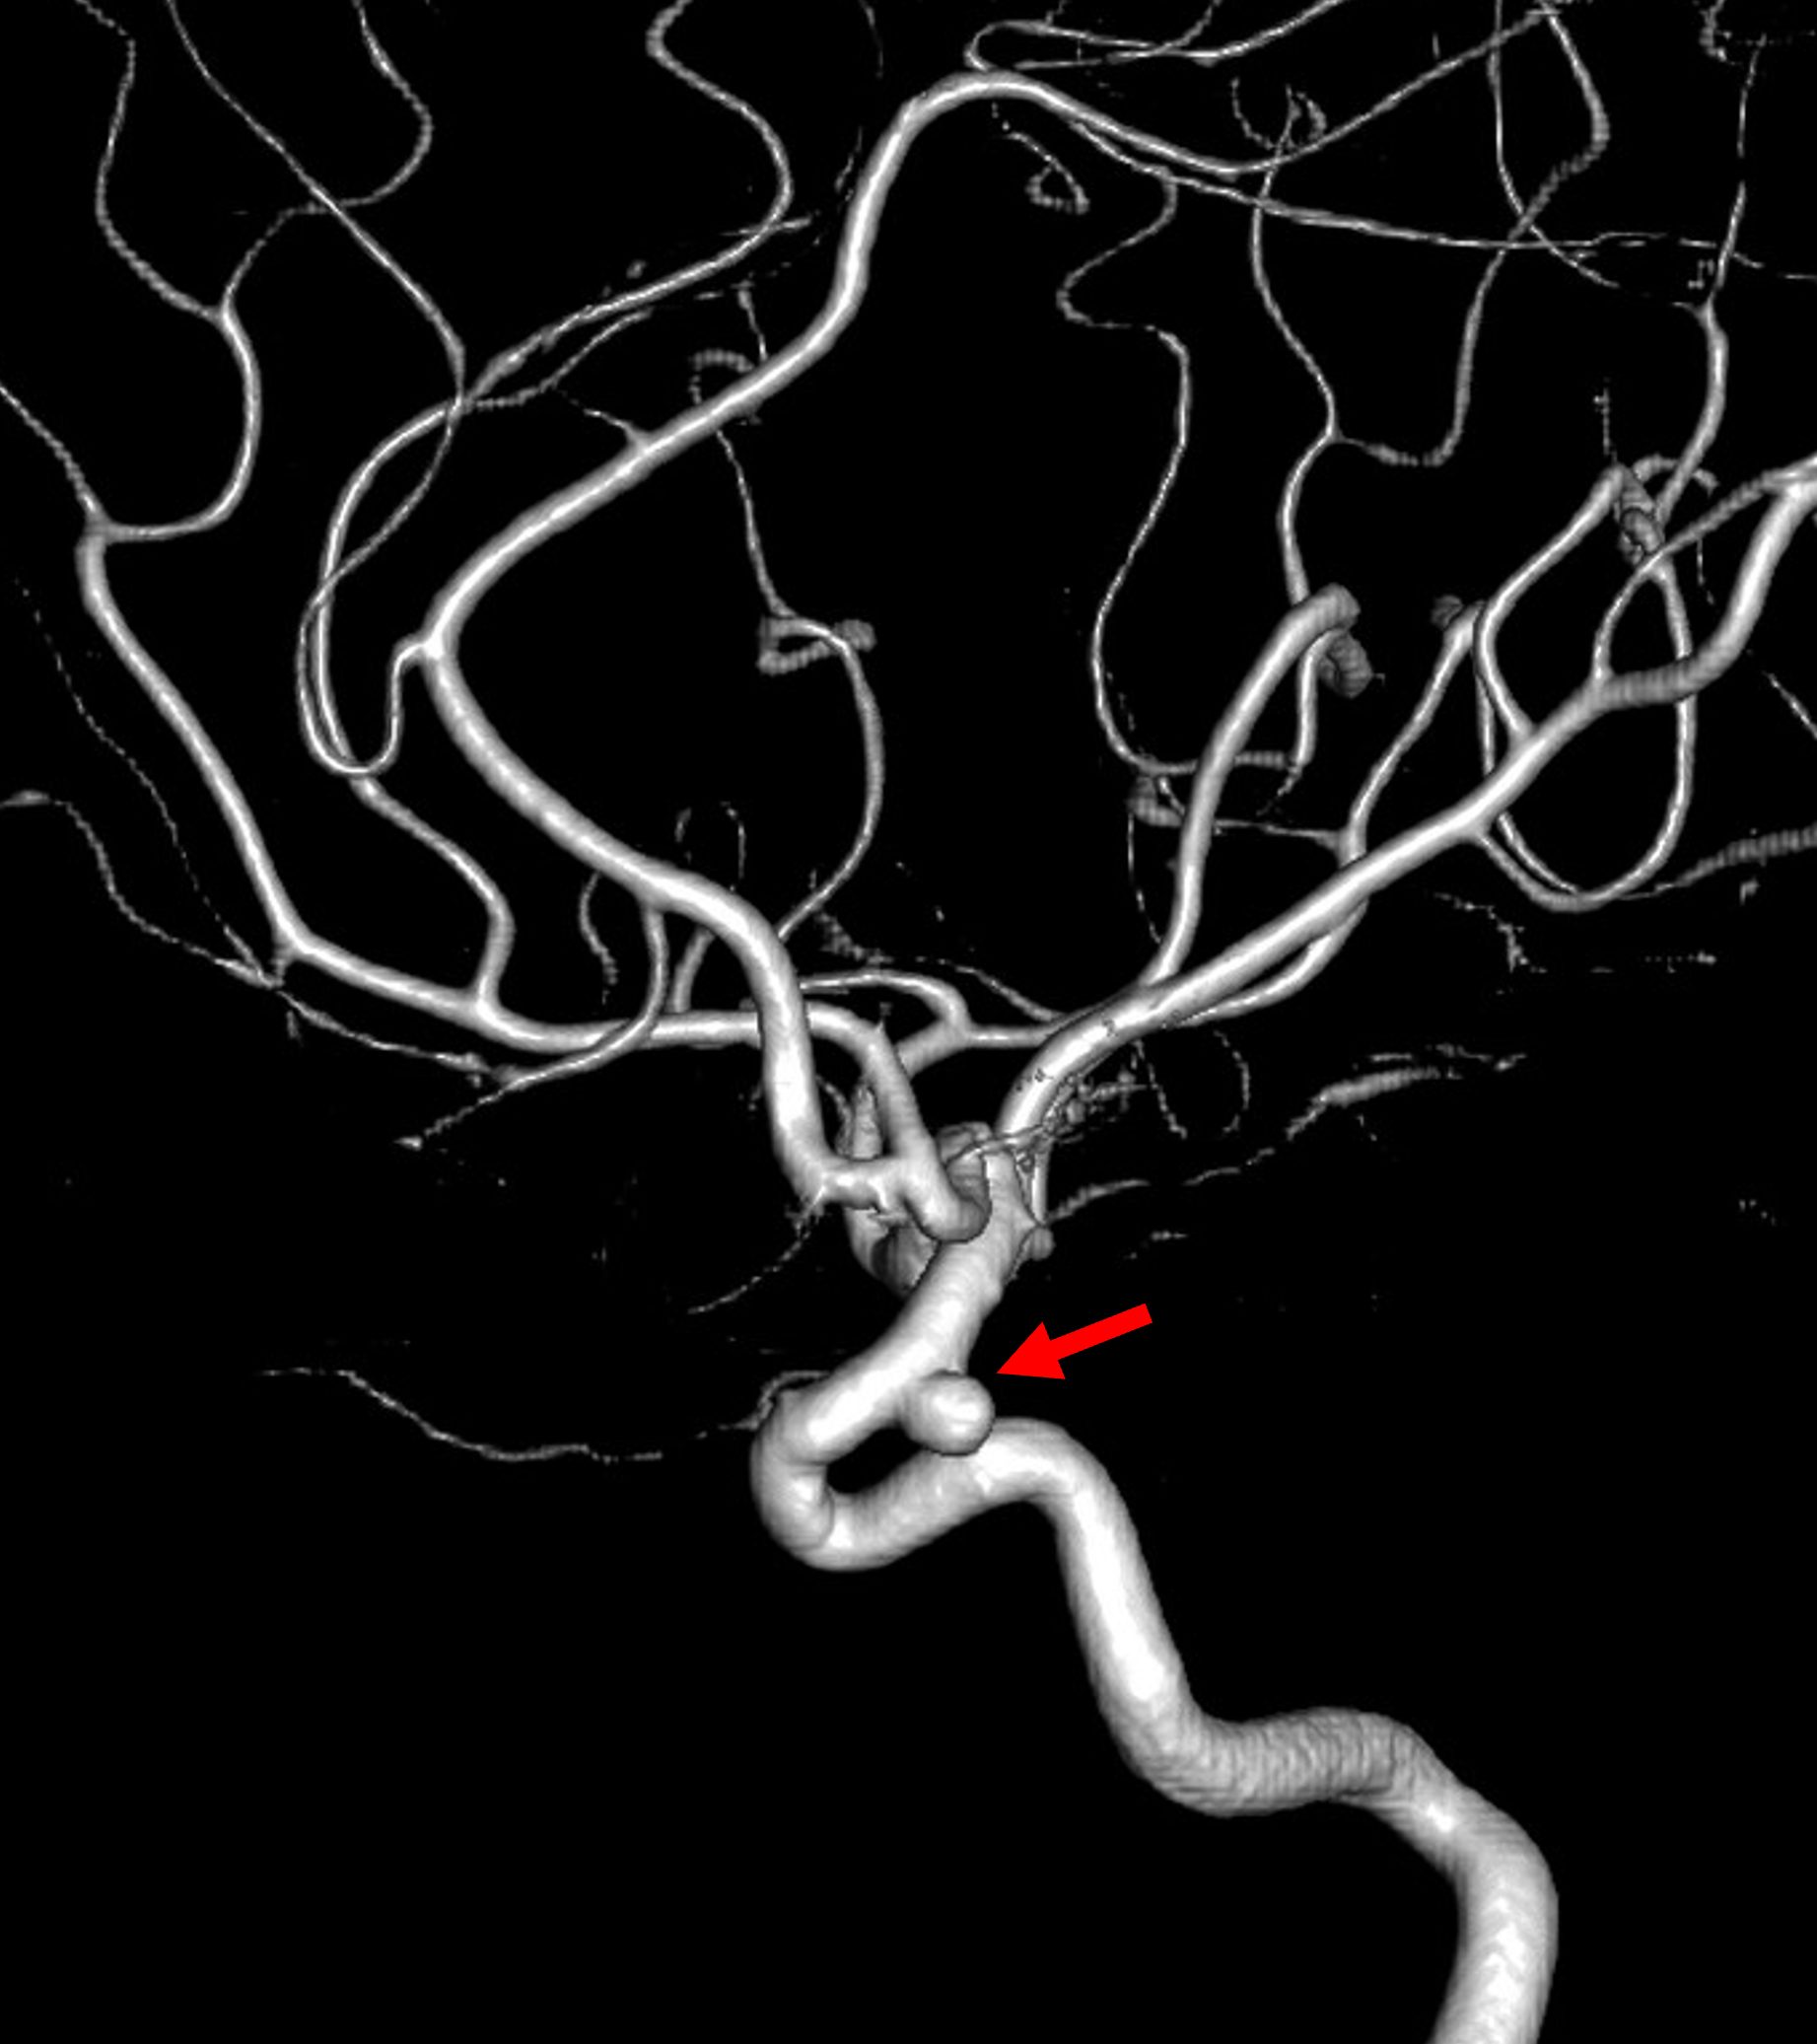

「脳卒中ガイドライン2021」によると、破裂率は脳動脈瘤の最大径と相関するため、5〜7mm以上の脳動脈瘤は治療が推奨されます。また、5mm未満であっても、部位(前交通動脈、後交通動脈、椎骨脳底動脈系)や形状(不整形・ブレブなど)の項目に該当する場合は、破裂の危険性が高いとされ、治療等について慎重に検討する必要があります。

未破裂脳動脈瘤の自然歴(破裂リスク)についての多くの研究をまとめると、破裂の危険性を高める因子としては、以下のようになります。脳動脈瘤の大きさは最も重要な要素ですが、たとえ小さい動脈瘤であっても部位や形状によっては破裂のリスクが高いとされます。また、経過観察中に脳動脈瘤の拡大や形状の変化が見られた場合の年間破裂率は極めて高いと報告されており、迅速な治療を検討すべきと考えられます。

開頭クリッピング手術と血管内治療があります。開頭クリッピング手術は、手術用顕微鏡下に脳動脈瘤の基部をクリップで閉鎖する治療法です。血管内治療は、脳動脈瘤内にコイルを挿入するコイル塞栓術です。近年、血管内手術については新しいデバイスの導入が進み、バルーンやステントを併用して、安全かつ確実に龍を閉塞する手技が確立されてきています。

クリッピング術とコイル塞栓術のいずれを選択するかは、患者背景(年齢、合併症など)や症状、脳動脈瘤の大きさ・部位・形状等を考慮のうえ慎重に検討されます。